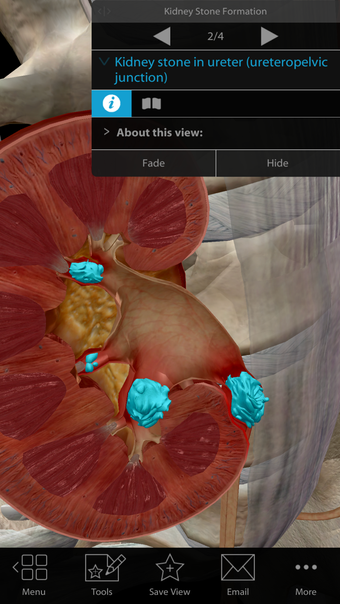

One of the most remarkable features of this application is that it enables users to compare 3D models of normal anatomy with models of common diseases and conditions. Furthermore, users can set the heart rate and visualize conduction in a dissectable, beating 3D heart while following along on an ECG. The application also presents animations that demonstrate the physiological processes of gas exchange, pulmonary ventilation, fluid balance, peristalsis, and more. Interactive lessons walk users through the progression of atherosclerosis, kidney stones, lung cancer, and other common conditions, and quizzes test users' knowledge of various physiological processes and pathologies.